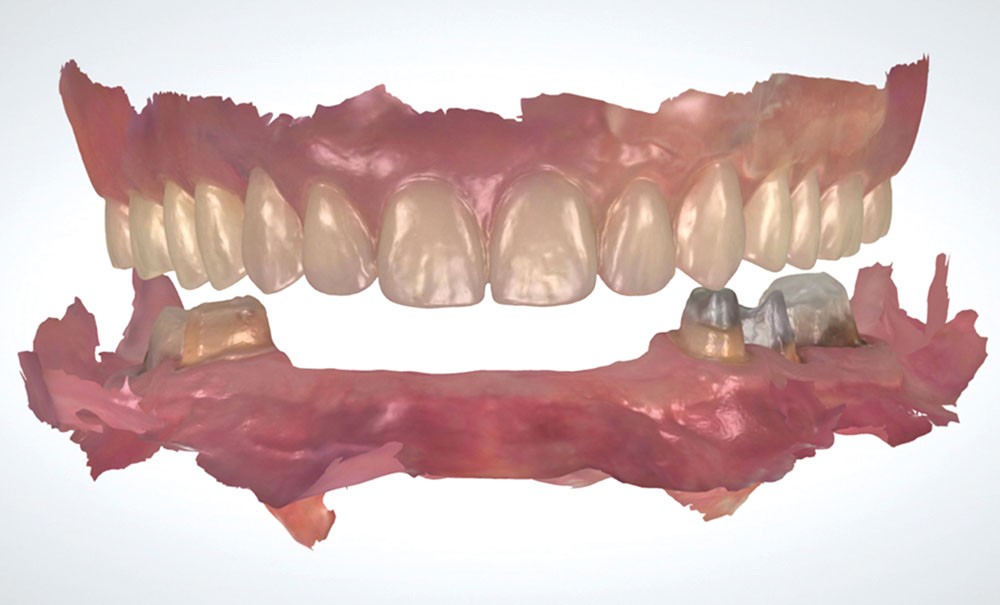

L’empreinte optique permet de positionner des points dans l’espace et l’ensemble de ses points crée le fichier 3D de l’empreinte. Ce référencement offre la possibilité d’enregistrer les arcades sans mordus ou cire d’occlusion dans les cas où le calage postérieur est absent (fig. 1).

Enfin, des outils d’analyse sont de plus en plus présents avec les systèmes d’empreinte, notamment pour analyser les épaisseurs préparées (avec des outils de coupe) ou pour étudier le parallélisme entre des dents dans les cas de bridge (fig. 2).

Lors de la préparation de piliers de bridge, la difficulté principale est de réussir à paralléliser correctement les piliers pour trouver un axe d’insertion pour la future prothèse. Là encore, l’empreinte optique facilite l’évaluation du parallélisme avec des outils très visuels et simples d’utilisation (fig. 8).